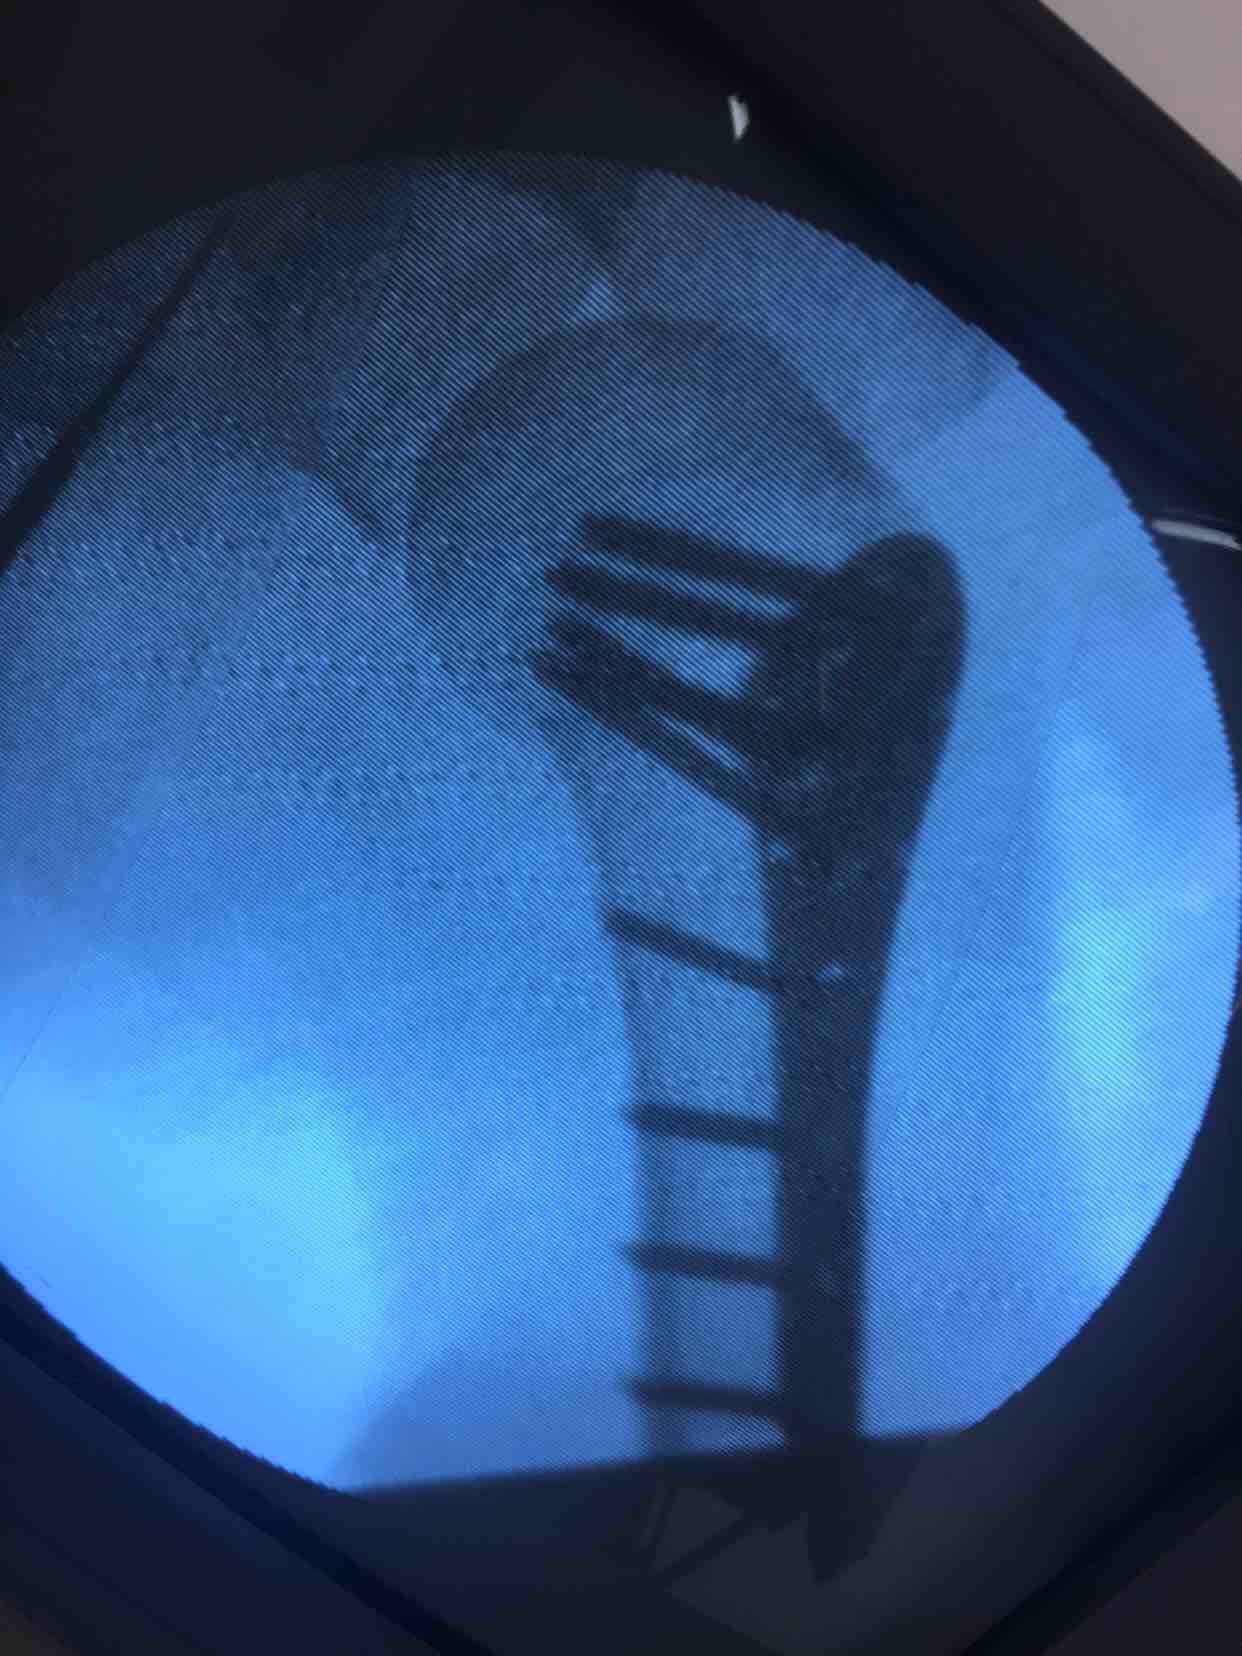

诊断:肱骨外科颈粉碎性骨折(右)完善术前准备,在臂丛麻醉下行切复内固定术,选肱骨近端锁定钛板,保持稳定性及早期功能锻炼。术后抗炎,消肿等处理。

手术最大优势尽可能解剖复位,保障骨折稳定,早期功能锻炼,避免肩肘腕综合征,骨折移位风险发生。